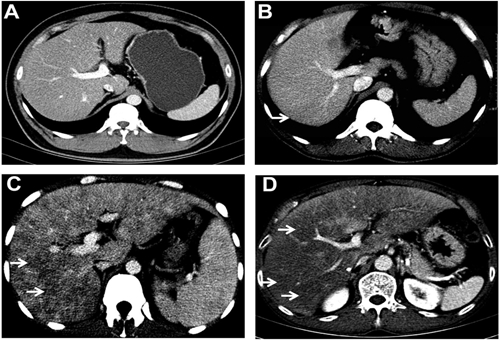

上腹部增強CT

例如當我們平掃時發(fā)現(xiàn)肝臟上發(fā)現(xiàn)一個低密度影,但是又不能確定這到底是一例肝癌、肝囊腫或者肝血管瘤或其他病變時,增強CT就派上了大用場!通過三期掃描,研究其血供情況可以判斷出病變種類。